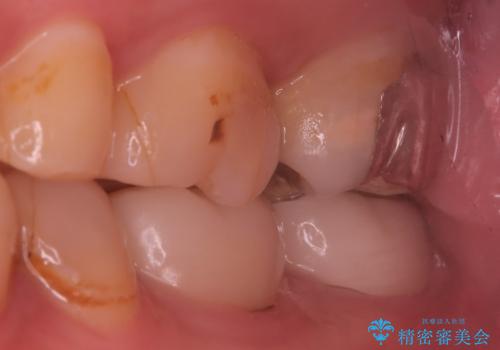

レントゲンや口腔内所見にて以下のような説明ののち、患者様が保存を希望されたため、当院では根管治療~オールセラミッククラウンにて修復処置を行いました。痛みも消えて、経過良好です。

治療選択肢として、①何もしない、②根管治療、③抜歯を説明した。

病気の原因は細菌であるため、細菌数を減らすための処置として一般的に②根管治療という選択肢がある。再根管治療の場合は病気が治るのは7割ぐらいであり、それでも治らない場合は意図的再植術を行い9割近くまで成功率を高めることができる。ただし、今回のケースでは根尖が湾曲しているため意図的再植時の破折リスクが高いため適応は難しい。また、根尖の病変が治ったとしても、歯周病、カリエス、脱離や破折リスクがあり治療後抜歯になる可能性もある。治らない可能性や治療したとしても抜歯になる可能性があることを考慮し、③抜歯の選択肢をとる場合もある。

であるならば、抜歯してインプラントも悪い選択肢とは言えないが、インプラント治療も同様に一生保存できると確約はできない。そのため、自分が患者の立場であるならば、少しでも長く自分の歯を保存し、最後の手段でインプラントを行う。そのためにできるだけのことをする。費用対効果が悪く感じるリスクがあったとしても、自分の歯を保存する価値は高いと考える。

今回の患者さんも同様に考えていたため、保存治療となったが、治療選択は患者さんの状況と術者の説明で変わるものである。